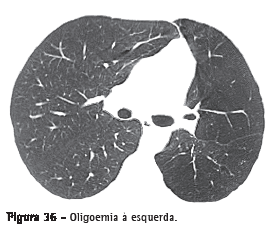

OligoemiaRedução focal, regional ou generalizada do volume sanguíneo pulmonar. A oligoemia apresenta-se como uma diminuição do calibre e do número de vasos pulmonares em regiões específicas ou difusamente, indicando que o fluxo sanguíneo é menor que o habitual (Figura 36).(3,7)